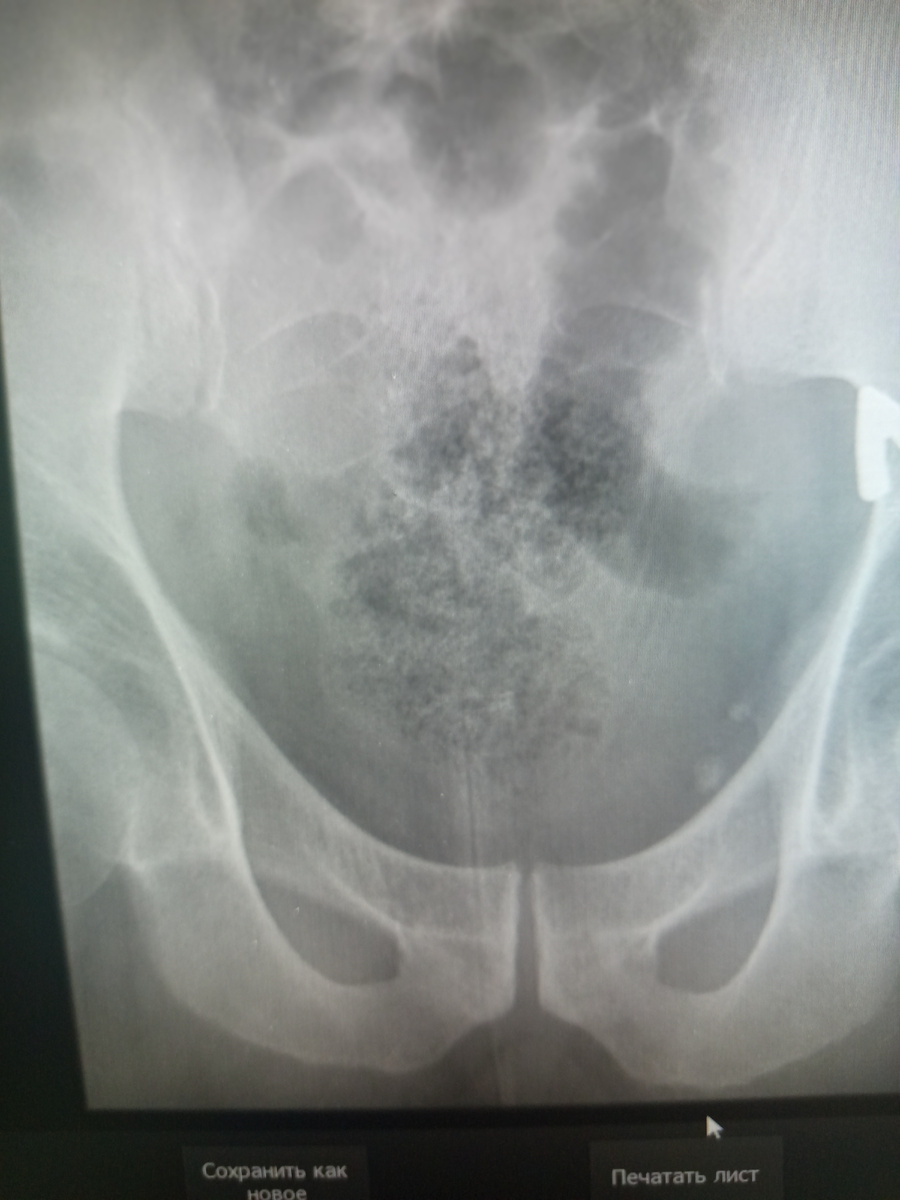

Исследования копчика на нашем приемнике в прямой проекции дело бесполезное , так как область исследования требует подготовки , в виде очистки кишечника , иначе мы получаем вот такой снимок.

-2

В боковой , конечно , уже другая картина, но , делаем , как полагается , две проекции , а вдруг , что называется?))